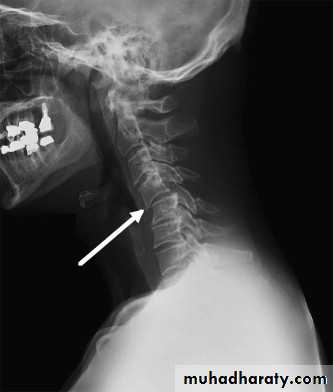

Spine injuries

Cervical classifications

extension subluxation

injuries of the cervical spine are usually caused by indirect violence,

Such as falls on to the head or

other violent movements transmitted from the skull. i.e in any direction.

A hyperextension

force may fracture the neural arch, especially of the atlas

Or fracture the dens (odontoid process) of the axis.

hyperextension may rupture the anterior longitudinal ligament and the

anulus fibrosus, forcing the vertebral bodies apart anteriorly (extension

subluxation) .

DIAGNOSISX RAY

Anterio posterior X ray radiograph.lateral radiographs with the head in flexion and extension may revealinstability that is not shown in the routine lateral film.

It is unnecessary to attempt reduction, and all that is required is to support the

neck for 2 months to relieve pain. This may be achieved by a rigid plastic Collar.